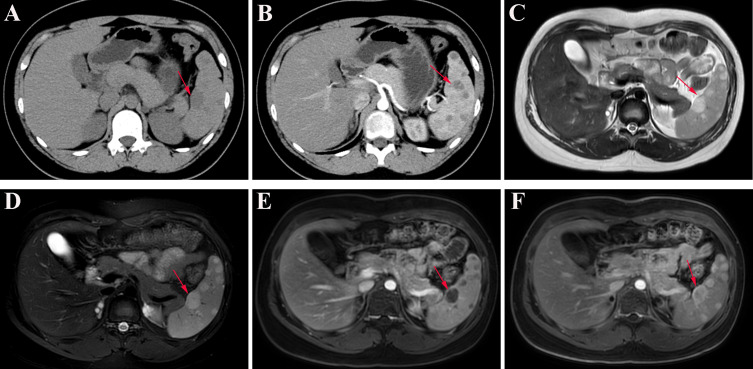

Case presentation: We observed a 14-year-old male who presented with intermittent abdominal discomfort and slight splenomegaly. Laboratory tests revealed no abnormalities. Computed tomography (CT) revealed diffuse splenomegaly with round or oval low-density lesions, suggestive of hemangiomatosis or lymphoma. Magnetic resonance imaging (MRI) revealed multiple lesions with slightly prolonged T1 and T2 signals. A CT-guided percutaneous biopsy of a splenic lesion was performed to address splenomegaly and diagnostic uncertainty. Histopathological examination confirmed diffuse splenic hemangiomatosis with lymphocytic infiltration.